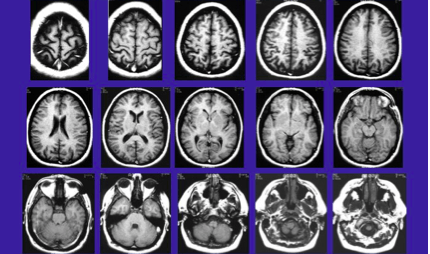

T1 sekvenca podrazumijeva kratka TR i TE, a koristi se za otkrivanje i diferencijaciju osnovnih anatomskih elemenata na učinjenom presjeku.

U T2 sekvenci se koriste duga TR i TE vremena, a koristi za izdvajanje patoloških promjena od normalnih elemenata tkiva.

Ovdje je prikazan kranijum u transverzalnoj ravni u T1 i T2 vremenu. Uočljiva je razlika koja ukazuje na to da je u T1 vremenu bijela masa svjetlija, u odnosu na sivu masu i cerebrospinalnu tečnost, dok su u T2 vremenu ove strukture predstavljene kao negativ T1 vremena.